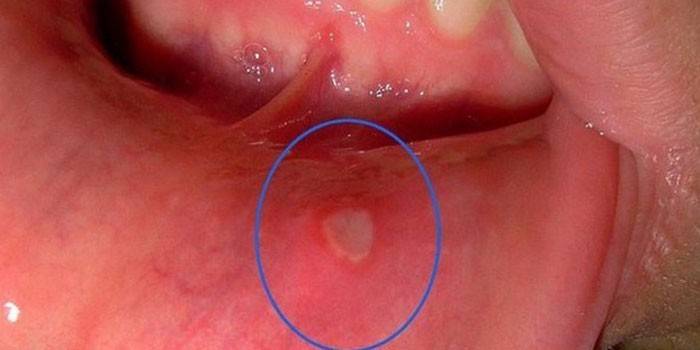

- aftózna stomatitída;